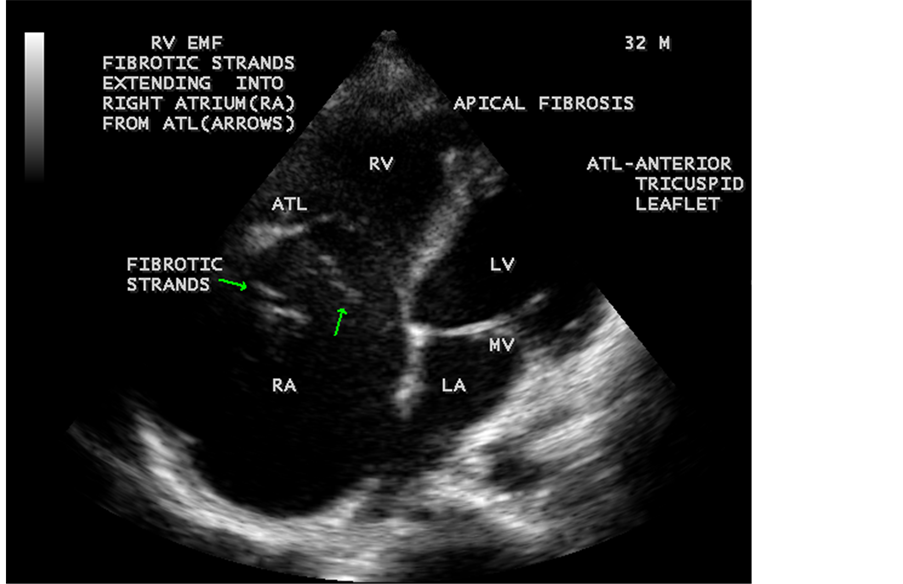

Figure 35. Endomyocardial fibrosis showing thick fibrous strands in the right atrium in a 32- year-old male and a dilated right atrium.

Figure 39. Right ventricular Endomyocardial fibrosis mimicking as Ebstein anomaly in a 32- year-old male. (subendocardial inflammation spreads to endocardium and results in formation of mural thrombi, which becomes organized and undergo fibrotic change, usually begins in the delicate inflow tract and involves the apex. The apical obliteration and subvalvular fibrosis reduces the size of RV cavity leading to an apparent downward displacement of tricuspid valve which is exaggerated by giant right atrium and mimic Ebstein’s anomaly).

When the endocardium is replaced by collagenous fibrosis (consists of collagen deposition and fibroblast proliferation), the final fibrotic stage is reached after several years of disease activity. Fibrotic obliteration of the apices of the affected ventricles is the hallmark of the disorder and fibrosis involving the papillary muscles and chordae tendineae leading to atrioventricular valve distortion and regurgitation. In the left ventricle, the fibrosis extends from the apex to the posterior mitral leaflet, usually sparing the anterior mitral leaflet and outflow tract and cause PML (posterior mitral leaflet) distortion and regurgitation. Like the peculiar geographical distribution, the fibrotic endomyocardial involvement stops short of the ventricular outflow tract like a ridge [17] as shown in Figure 15, Figure 29, Figure 31, Figure 35 and Figure 45. The fibrotic tissue often creates a nidus for thrombus formation, which can be extensive. Atrial thrombi also occur and the right atrium may be aneurysmally dilated. Aneurysmal right atrium with spontaneous echo contrast was detected in a 32-year-old male as shown in Figure 36 ( [18] , Figure 3]). In addition, there are fibrosis and granular septation extending into the underlying myocardial tissue and myocyte hypertrophy is common [19] . Fibrotic process causes tethering of leaflets into ventricular walls and may mimic Ebstein’s malformation as shown in Figure 39 and Figure 66 [20] [21] . Fibrosis increases the stiffness of the heart, resulting restrictive physiology, AV (atrioventricular) valve regurgitation which has been linked to atrial arrhythmias such as atrial fibrillation as shown in Figure 19 and Figure 20 in a 62-year-old female. Atrial fibrillation has been reported in more than 30% of patients with EMF. Fibrosis impairs activation patterns of the conduction system and may provide substrate for wave breaks and reentry [22] . Fibrosis reduces conduction velocity and cause conduction abnormalities like junctional rhythms, heart blocks as shown in Figure 21 and Figure 22 in a 75-year- old female and atrioventricular conduction delay [23] .

enlargement as in Figure 33 are the characteristic features of advanced stage of EMF. The fibrosed muscular trabeculae extending into the cavities from the walls of the chambers in the right ventricle visible as “cobra heads” as in Figure 4 and in pericardial sac as in Figure 29. Aneurysmal right ventricle with scattered areas of fibrosis in the sub tricuspid region and a notch in the right atrium is well seen in a 14-year-old boy as in Figure 43. Right atrial notch is frequently noticed in EMF patients as shown in Figure 42 in a 47-year-old male with left ventricular EMF and moderate pericardial effusion.